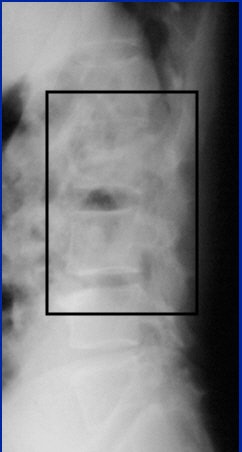

CT has advanced and now offers information that x-rays cannot begin to provide, he noted, citing the case shown below (images A-E).

Image A

"Here the patient has an L-2 fracture that you can see. Notice the quality of the image isn't very good. That's important because in the trauma setting, you can't always get good-quality images. You can make the diagnosis of an L-2 fracture on the plain films, but you can't characterize it until you get to CT," Cinnamon explained.